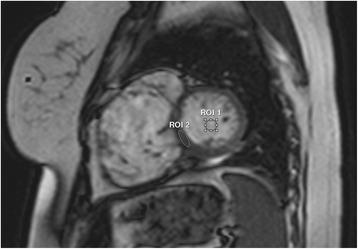

This retrospective, cross-sectional study included all patients ≤18 years old or with congenital heart disease who underwent CMR on an open 1.0 Tesla scanner at two centers from 2012-2014. Indications for CMR and clinical questions were extracted from the medical record. Studies were qualitatively graded for image quality and diagnostic utility. In a subset of 25 patients, signal-to-noise (SNR) and contrast-to-noise (CNR) ratios were compared to size- and diagnosis-matched patients with CMR on a 1.5 Tesla scanner.

A total of 65 patients (median 17.3 years old, 60% male) were included. Congenital heart disease was present in 32 (50%), with tetralogy of Fallot and bicuspid aortic valve the most common diagnoses. Open CMR was used due to scheduling/equipment issues in 51 (80%), claustrophobia in 7 (11%), and patient size in 3 (5%); 4 patients with claustrophobia had failed CMR on a different scanner, but completed the study on open CMR without sedation. All patients had good or excellent image quality on black blood, phase contrast, magnetic resonance angiography, and late gadolinium enhancement imaging. There was below average image quality in 3/63 (5%) patients with cine images, and 4/15 (27%) patients with coronary artery imaging. SNR and CNR were decreased in cine and magnetic resonance angiography images compared to 1.5 Tesla. The clinical question was answered adequately in all but 2 patients; 1 patient with a Fontan had artifact from an embolization coil limiting RV volume analysis, and in 1 patient the right coronary artery origin was not well seen.